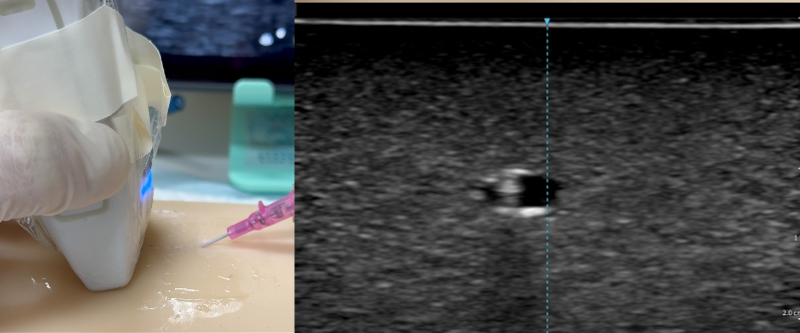

- Slide the probe: Slide the probe distally until the dot disappears. Do not tilt the probe.

- Advance the needle: Move the needle until the needle tip reappears and stop immediately. The needle tip should appear closer to the vessel this time.

- Stop the needle and slide the probe away

- Tent the vessel wall and pop it